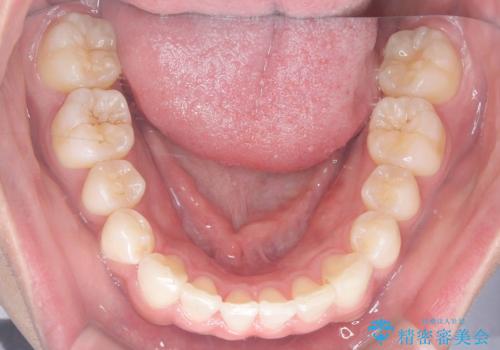

歯のデコボコを治したい|インビザラインで綺麗な歯並びに!|矯正期間は6ヵ月!

- 歯のデコボコが気になるを主訴に来院された患者様です。

インビザラインで歯は抜かずに非抜歯でデコボコを改善しました。

インビザラインで叢生の改善を行いました。

歯は抜かずに、拡大と少しのIPRで並べました。

矯正期間は半年です。

綺麗な歯並びを手に入れ大変ご満足していただきました。